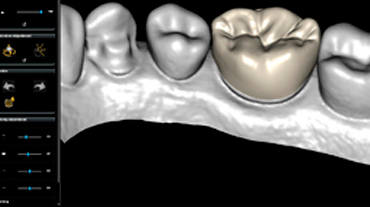

CS Restore

Diseño de restauraciones rápido, sencillo y automático